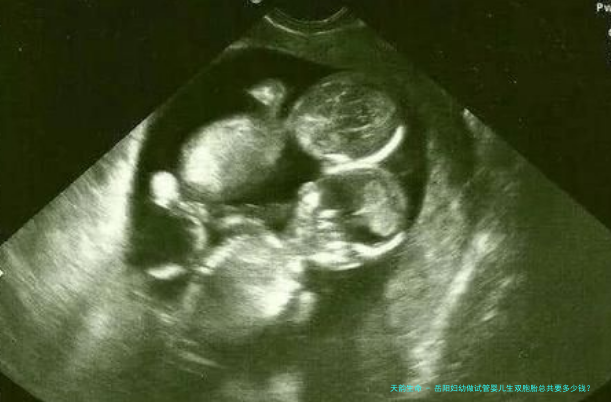

相关推荐 问答文章 无锡市妇幼保健院试管双胞胎费用大概多少?在无锡市妇幼保健院做试管双生子的费用,一般来说,总费用大约在5万元到10万元元钱之间。这一笔费用会涵盖多项,囊括术前检查费用(男女两方),促排卵药物费用,取卵手术及胚胎培育费用,胚胎移植手术费用,

无锡试管婴儿 试管双胞胎婴儿费用 2小时前·46人浏览 去贵阳市妇幼做试管怀双胞胎需要多少费用?在贵阳市妇幼保健院做试管婴儿,如若计划是怀双生子,总价格大致在5万元到10万元之间。这个费用并非固定,会受到许多种因素影响,比如使用的诱导排卵药物类型、移植的胚胎数目、以及是否需要进行额外的辅助治疗等。贵

在东阳人民医院做试管婴儿怀双胎的费用,在一般情况下,整个流程下来大约需要4万元到八万元元钱。这个费用并不是牢固稳定,它会受到很多要素的影响,例如使用的促排卵药物品类和使用量、病人的健康状态、以及需不需要进行

试管双胞胎婴儿费用 4小时前·47人浏览 去六安中医院做试管怀双胞胎需要多少费用?在六安传统医学院做试管婴儿,如果想怀孪生儿,费用会比单胎略高一些。一般来说,一个周期的试管费用大约在三万块到六万元之间。这中间含有了术前检查费用、诱导排卵药物费用、采卵手术费用、胚胎培养费用、胚胎移植费

六安试管婴儿 试管双胞胎婴儿费用 20小时前·50人浏览 临沂中心医院试管婴儿生双胞胎价格明细表有吗?临沂中心医院并没有提供特意的试管婴儿生双胞胎价格明细表。试管婴儿的费用会根据病人的详尽情形、所所用促排卵方案以及移植的胚胎数量而有所差异。在临沂中心医院进行一次完整的试管婴儿周期,囊括术前检查、促排

临沂试管婴儿 试管双胞胎婴儿费用 1天前·35人浏览 枣庄市立医院试管婴儿生双胞胎价格明细表有吗?枣庄市立医院目前没有官方发表的针对试管婴儿双胞胎的特定多少钱明细表。在一般情况下,试管婴儿的总费用会根据个人情况和所所使用技术而略有差异,双胞胎的费用并不会比单胞胎高太多,主要影响因素还是在于促排卵药物的使用

枣庄试管婴儿 试管双胞胎婴儿费用 1天前·27人浏览 详细解读阜阳试管婴儿的费用构成:2025年约10到20万元!近几载来,随着辅助生育技术的不断发展和人们对生育需求的增多,试管婴儿技术受到了越发越多的注意。许多不孕不育夫妇将盼望寄与于试管婴儿,而费用问题则就是他们最主要考虑的因素其中之一。本文将针对“